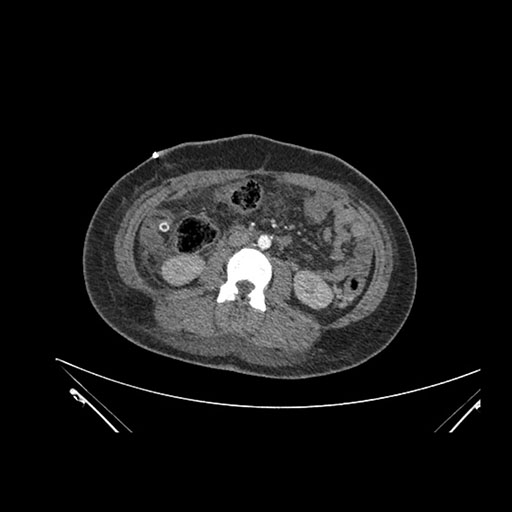

Imaging Analysis

Look through the patient's CT scan to identify any areas of concern for the necessary procedure.

Axial Venous